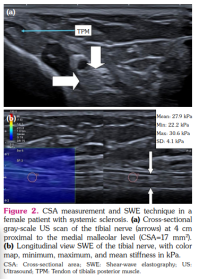

Tibial nerve was examined in the transverse and longitudinal planes at a distance of 4 cm proximal to the tip of the medial malleolus. The correct imaging plane was confirmed by tendinous landmarks, such as the flexor digitorum longus and flexor hallucis longus tendons, and the posterior tibial vessels.[16] CSA was measured by the use of a continuous boundary trace of the nerve directly over the epineurium on transverse images (Figures 1, 2).

Shear-wave elastography was performed by careful handling of the transducer during transport and mounting to avoid compression force. The skin surface was coated with ample coupling gel before placing the transducer, which was used with light force and kept stable during image acquisition. TN was first identified transversely, and then the transducer was rotated 90° to acquire a longitudinal image of the nerve in the parallel direction to the fiber orientation.[16]

The mean CSA value was 22±5.7 mm2 in patients with SSc and 12.65±3.4 mm2 in healthy controls. The mean stiffness value was 23.12±14.5 kilopascal (kPa) in patients with SSc and 15.5±3.27 kPa in healthy controls. The CSA and stiffness values of the right TN were significantly higher in SSc patients than in healthy control subjects (p<0.001 and p=0.015, respectively; Table 2).